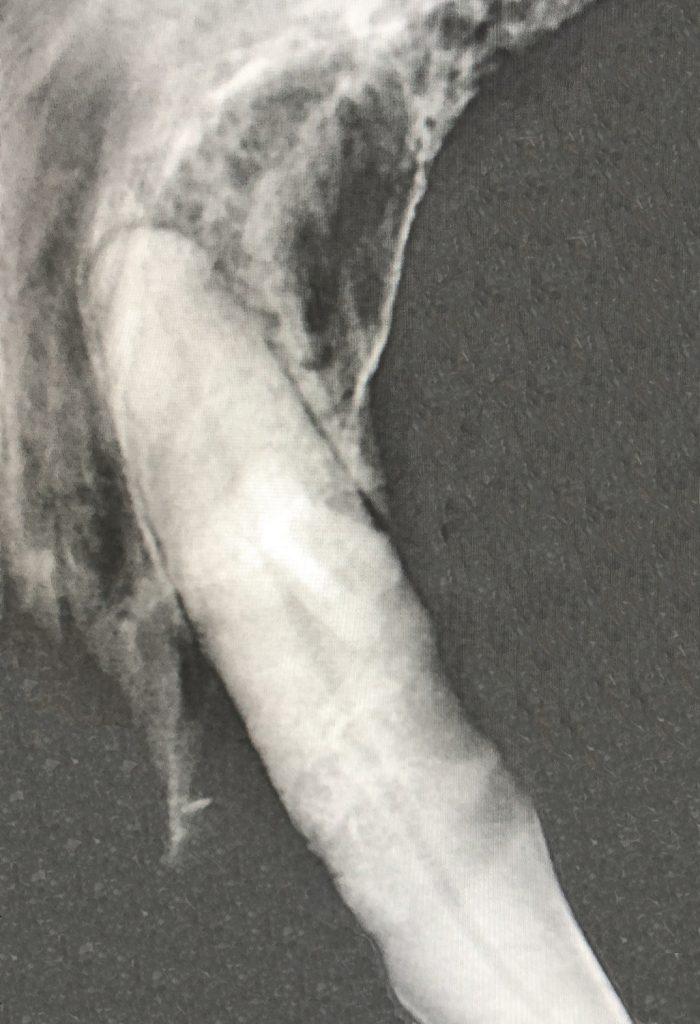

Röntgenfoto’s

Röntgenfoto’s kunnen gemaakt worden voor problemen met de botten en gewrichten, de urinewegen, het maag- en darmstelsel of voor het hart en de longen. Helaas is niet altijd alles zichtbaar en kan het nodig zijn om het onderzoek te combineren met bloedonderzoek of echografie.

Voor een röntgenfoto hoeft een dier niet per se onder sedatie gebracht te worden. Zeker bij hart- of longpatiënten, die toch al een risicogroep zijn, doe je dit liever niet. Voor botbreuken en gewrichtsproblemen juist weer wel, omdat deze patiënten vaak pijn hebben. Daarnaast is het makkelijker om het dier in de juiste positie te leggen.

Aangezien röntgenstraling potentieel gevaarlijk is, mogen zwangere vrouwen en baasjes onder de 18 jaar niet meehelpen met het maken van de foto’s. Onze ervaren paraveterinairen nemen de patiënt over van de eigenaar, waarna er 2 (of eventueel 3) opnames gemaakt worden in de röntgenkamer. Eén waarbij het dier op de zij ligt en één terwijl hij of zij op de rug of de buik ligt. Bij controle voor uitzaaiingen in de longen worden er 3 opnames gemaakt, één extra op de andere zijde. Doordat er in meerdere richtingen een foto wordt gemaakt, kan er een driedimensionaal beeld gevormd worden. Dit is essentieel voor de diagnostiek en het behandelplan. Hiermee kan een indicatie van de preciezere lokalisatie van het probleem gevonden worden.

Ook beschikt onze kliniek over een dentale röntgenbuis. Hiermee kunnen tijdens gebitsbehandelingen (onder narcose) de wortels van de verschillende gebitselementen zichtbaar gemaakt worden, zodat gerichter problemen behandeld kunnen worden. Het kan helpen in het bepalen of er elementen verwijderd moeten worden of kunnen blijven zitten. Deze röntgenbuis is speciaal voor kleine onderdelen en kan daardoor ook gebruikt worden voor middenvoetsbeentjes of kleine knaagdieren en konijnen.